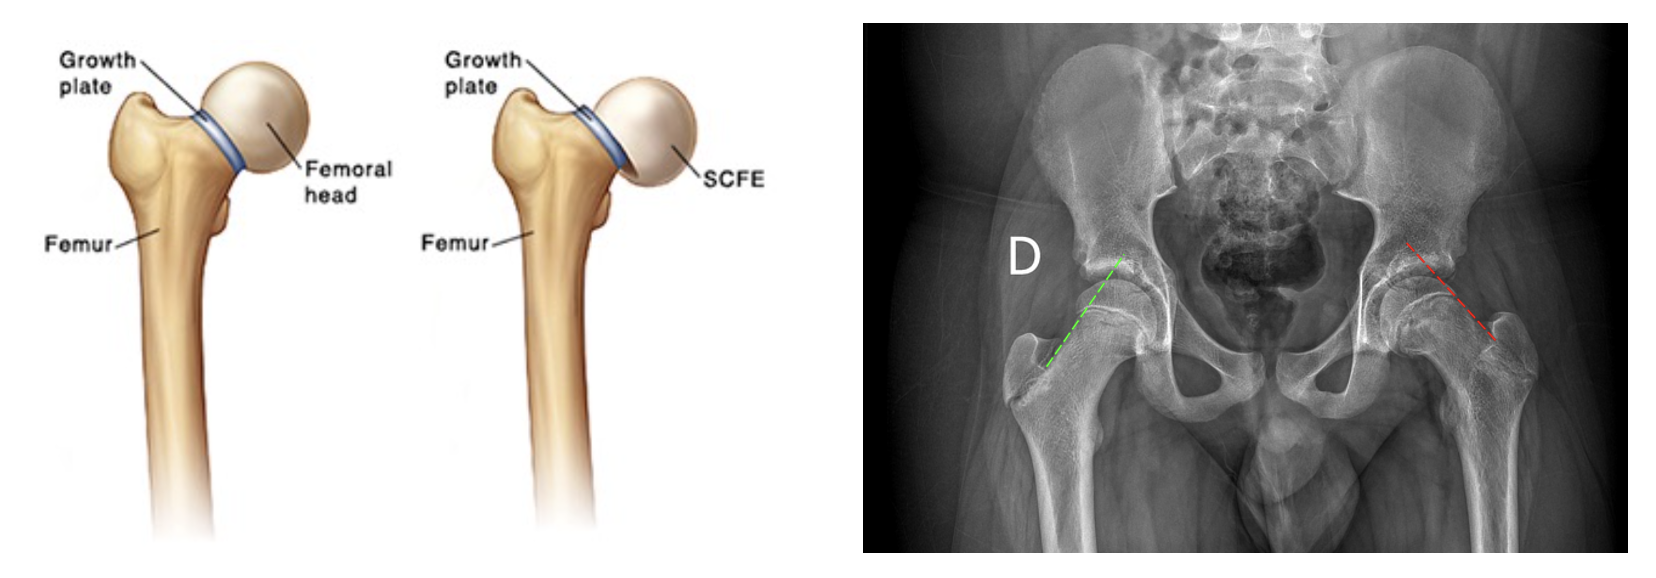

• 정의: 대퇴골 경부(metaphysis)에 대해 골단(epiphysis)이 성장판(physis)을 따라 후내측(postero-inferior)으로 전위(slip)

• X-ray (AP & Frog-leg lateral view):

• AP view: Klein's line (대퇴 경부 상연선)이 골단을 통과하지 않거나 스침

• Frog-leg lateral view: 후방 전위(posterior slip) 확인에 가장 민감함